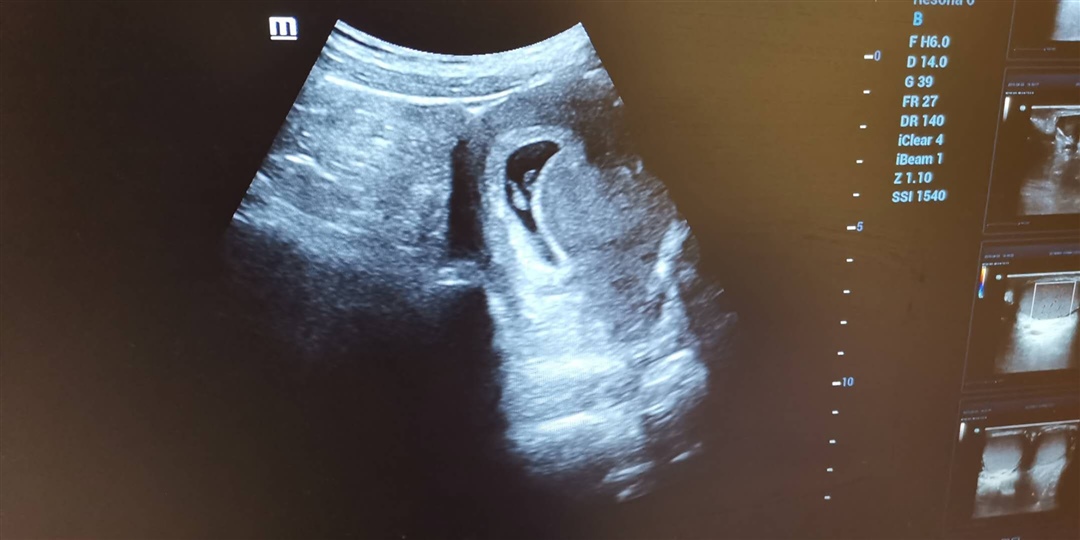

孕11周+2天

我10周的时候吃的维生素b6当天就不吐了,还的我瞎想了一个礼拜,今天产检都可以用仪器检测出来胎心声音了……放轻松

湘湘:我是8周b超检测到胎芽和心管搏动,今天11周可以用胎心监测仪听到声音的